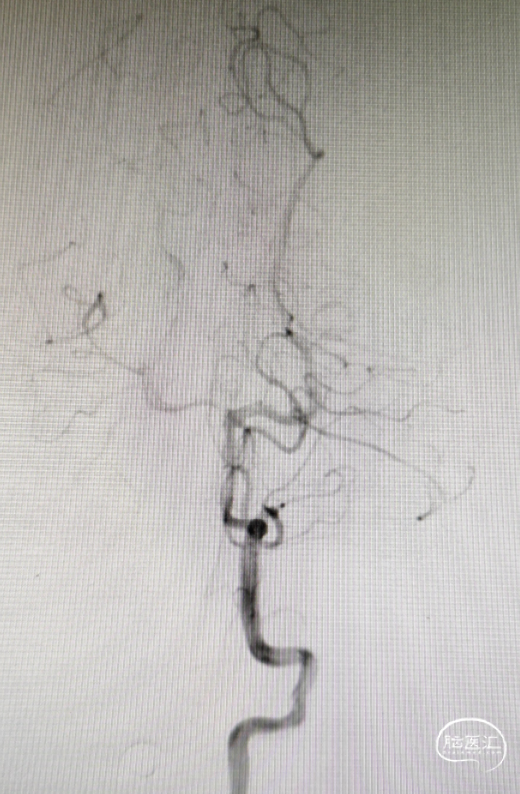

DSA造影确认前交通动脉瘤、左侧大脑中M1段分叉部动脉瘤。

①以Seldinger技术经右侧股动脉穿刺,造影后选取工作位并建立路径图;

②瘤体多分叶,采用双系统填圈;

同侧释放一枚LEO Baby支架 2.5*18mm。

通过微导管1依次置入4*8、3*4、2*6、2*4、2*2mm五枚弹簧圈。

造影见对侧大脑前显影稍差,考虑瘤颈处血栓形成;遂给予静脉团注10ml替罗非班(0.05mg/ml),同时以5ml/h静脉泵注。

在右侧大脑前释放一枚LEO Baby支架 2.5*12mm,“Y”成型;

通过微导管2置入一枚1.5*2mm 弹簧圈后出现踢管;

造影见对侧大脑前血流恢复,远端瘤体已致密栓塞,但近端瘤体存在残留;

由于使用的为编织型支架,故结束手术不再填圈。